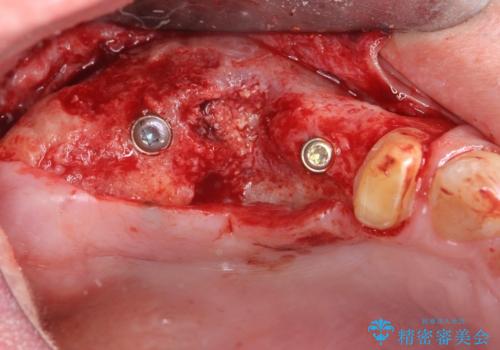

インプラント埋入時に骨の造成を、2次手術時に歯肉の凹みを整え厚みを一定にするような治療を進めていきます。

- 106.7万円 (インプラント×2 アバットメント×2 ジルコニアクラウン×3 骨造成 )費用は治療当時の料金となります

骨の造成、歯肉を整えたことで、術前山形にえぐれていた歯肉形の態はなだらかになり清掃しやすい状態へと整備することができました。